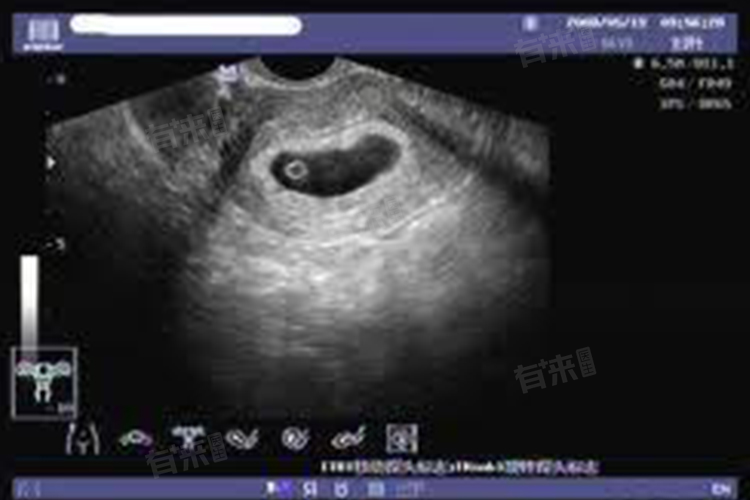

孕囊的形态和位置也需要特别注意,正常情况下孕囊应该是圆形或椭圆形的,并位于子宫腔内。如果孕囊形态异常或者位置不在子宫腔内,可能会考虑宫外孕等问题。超声检查不仅能够测量孕囊的大小,还能提供关于胚胎发育、子宫环境等信息,为判断怀孕是否正常提供依据。

1、超声检查:超声检查是评估孕囊大小的最基本方法。通过阴道超声或腹部超声,可以清晰地观察到孕囊的直径、形态及位置。若孕囊直径过小或过大,超声可以提供明确的影像数据,为进一步诊断提供依据。